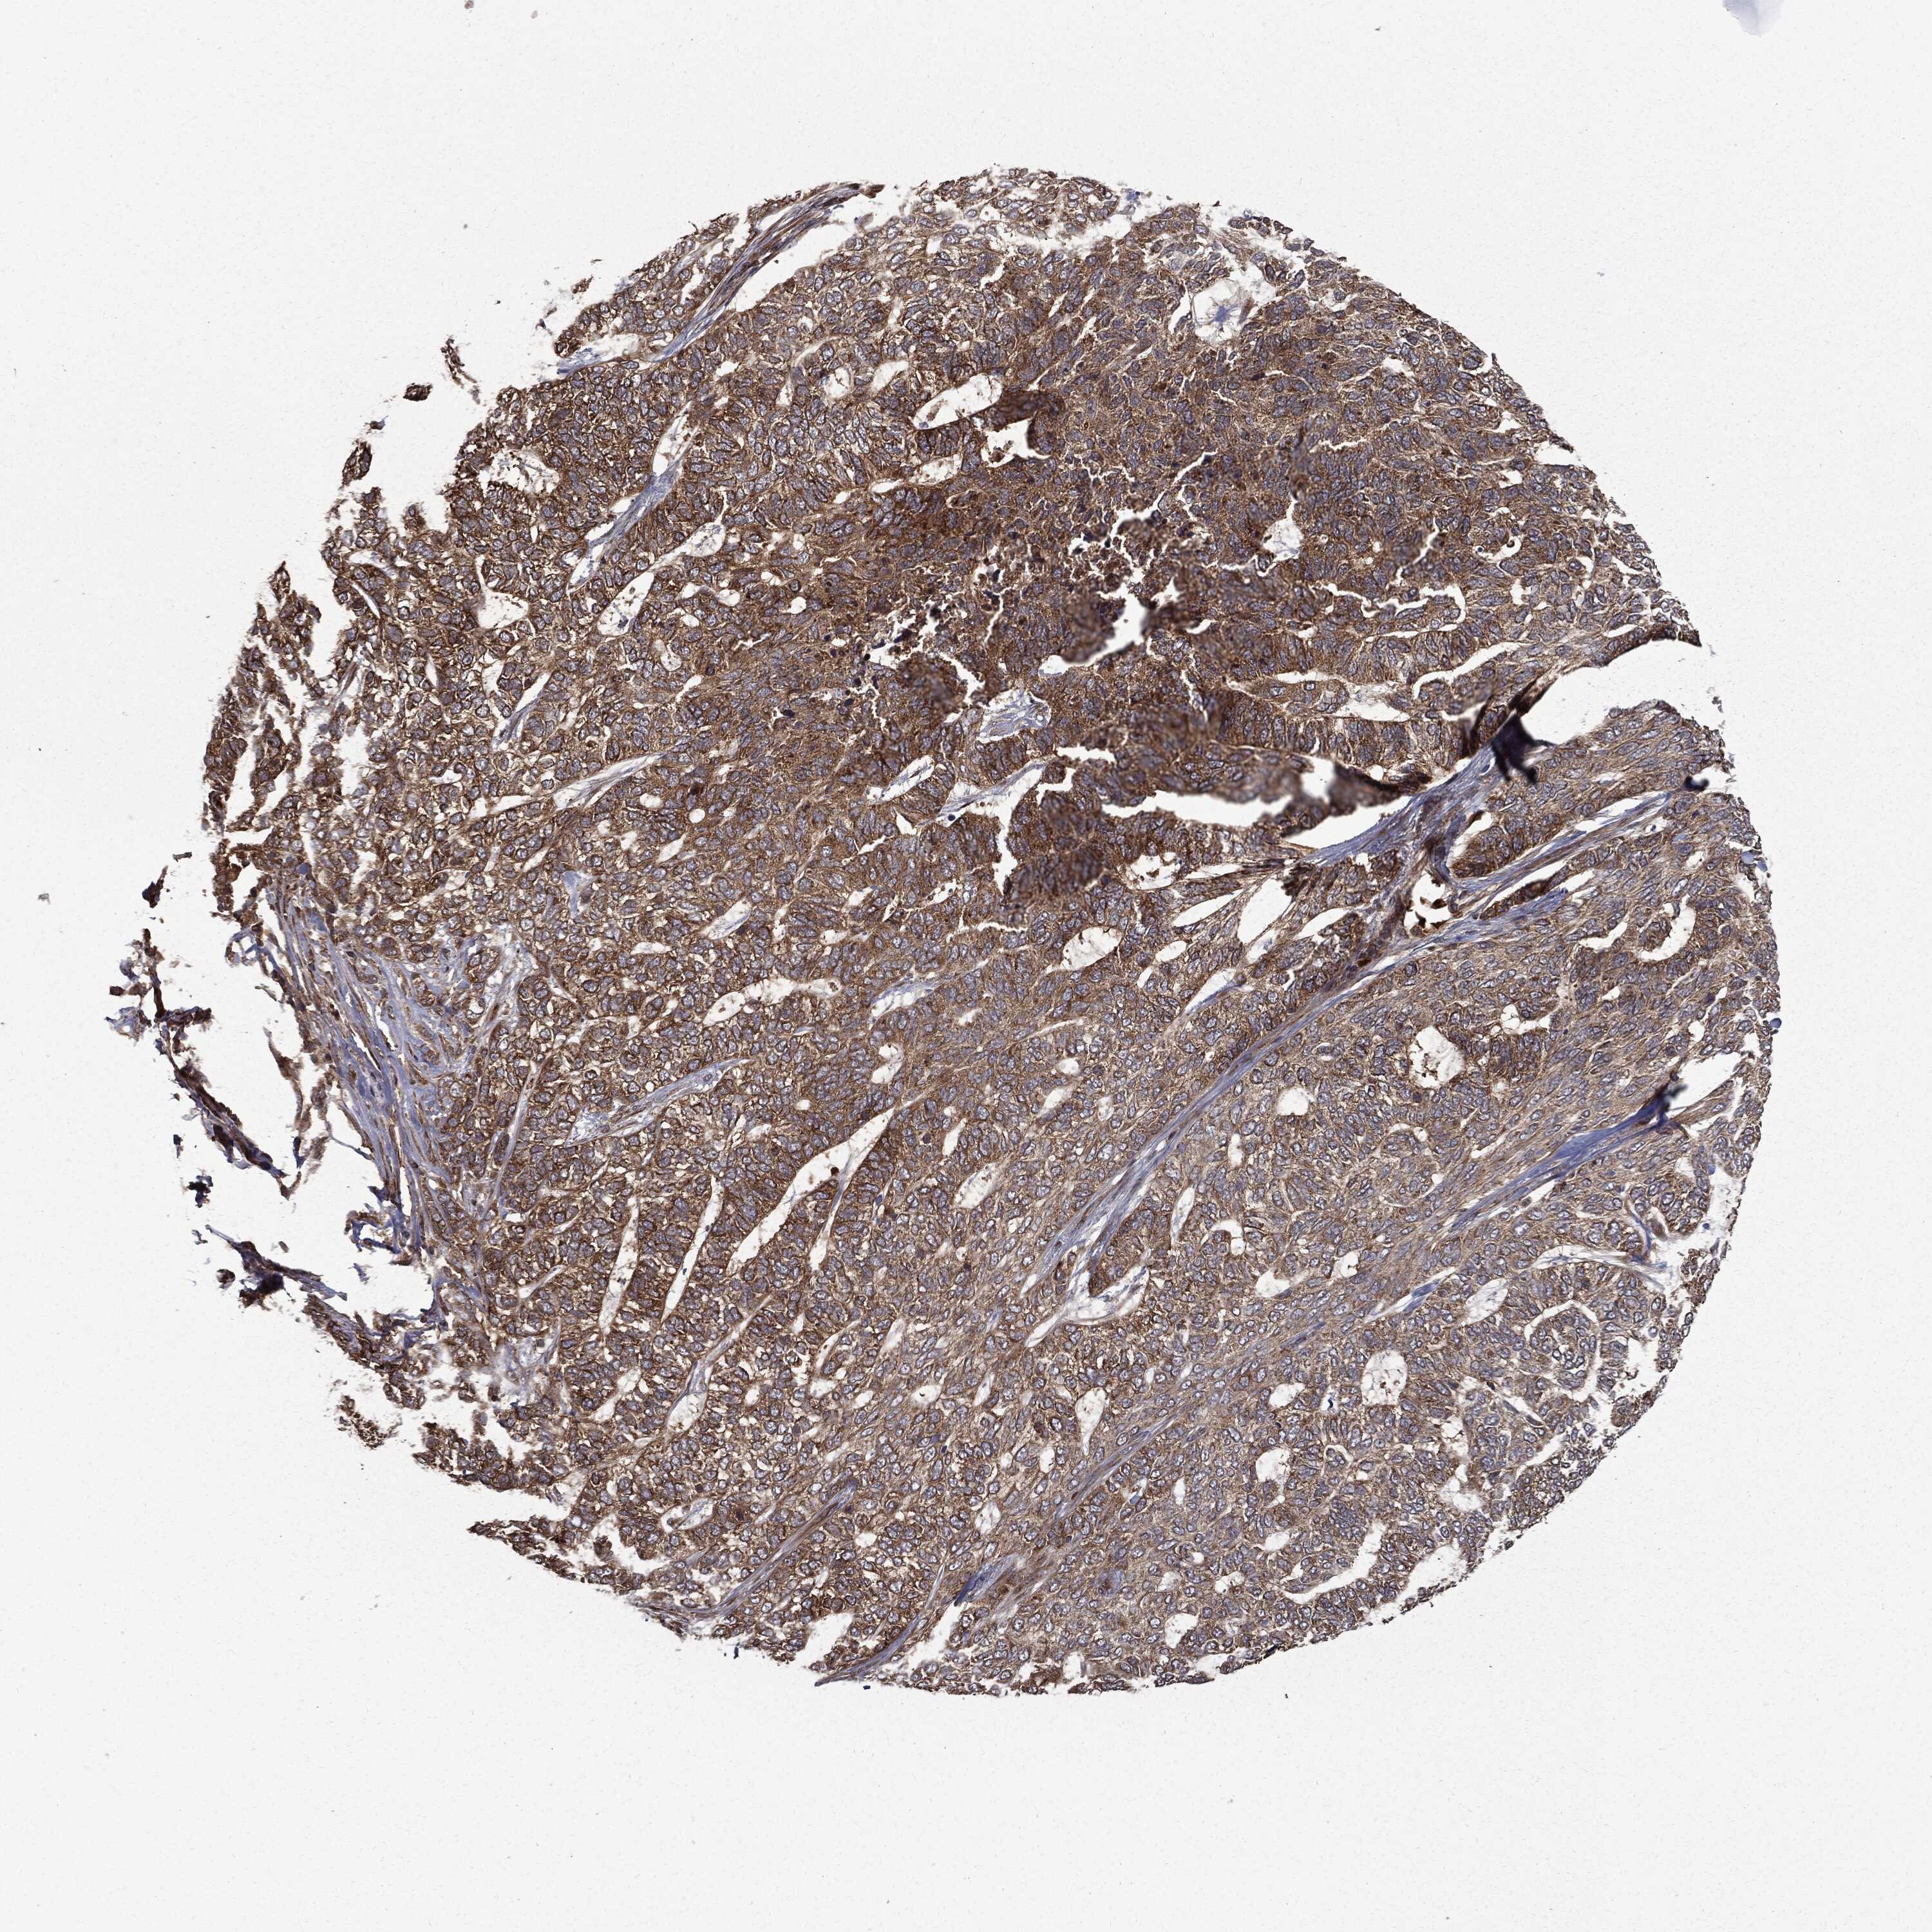

SKIN CANCER - Protein expressioni

A mouse-over function shows sample information and annotation data. Click on an image to view it in a full screen mode. Samples can be filtered based on level of antibody staining by selecting one or several of the following categories: high, medium, low and not detected. The assay and annotation is described here.

Each image is clickable and will lead to virtual microscopy that enables deeper exploration of all samples and also displays staining intensity scores, fraction scores and subcellular localization as well as patient and tissue information for each sample.

Antibody HPA026114

Antibody HPA051524

Antibody CAB002756

Staining

High

Medium

Low

Not detected

Intensity

Strong

Moderate

Weak

Negative

Quantity

>75%

75%-25%

<25%

None

Location

Nuclear

Cytoplasmic/membranous

Cytoplasmic/membranous,nuclear

Basal cell carcinoma

Squamous cell carcinoma, NOS

Squamous cell carcinoma, metastatic, NOS